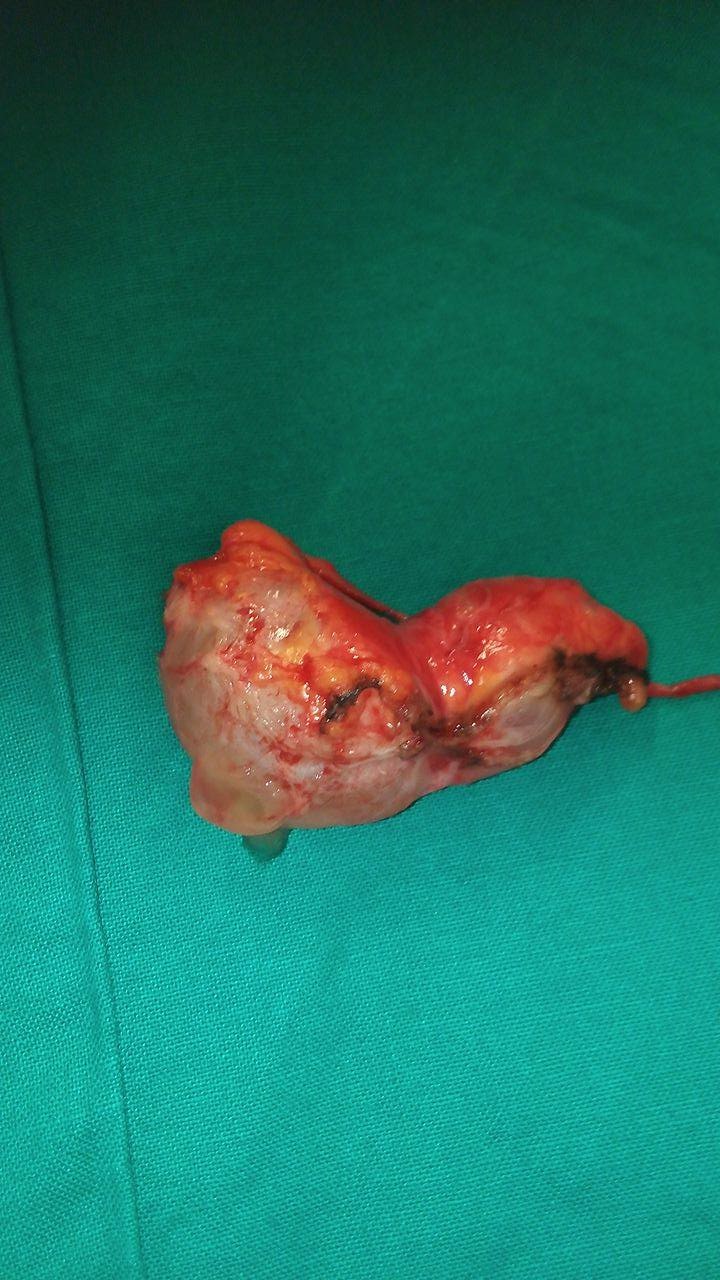

Χειρουργικά παρασκευάσματα ώριμου τερατώματος και σκωληκοειδούς (Ευγενική παραχώρηση Dr. V. Penopoulos)